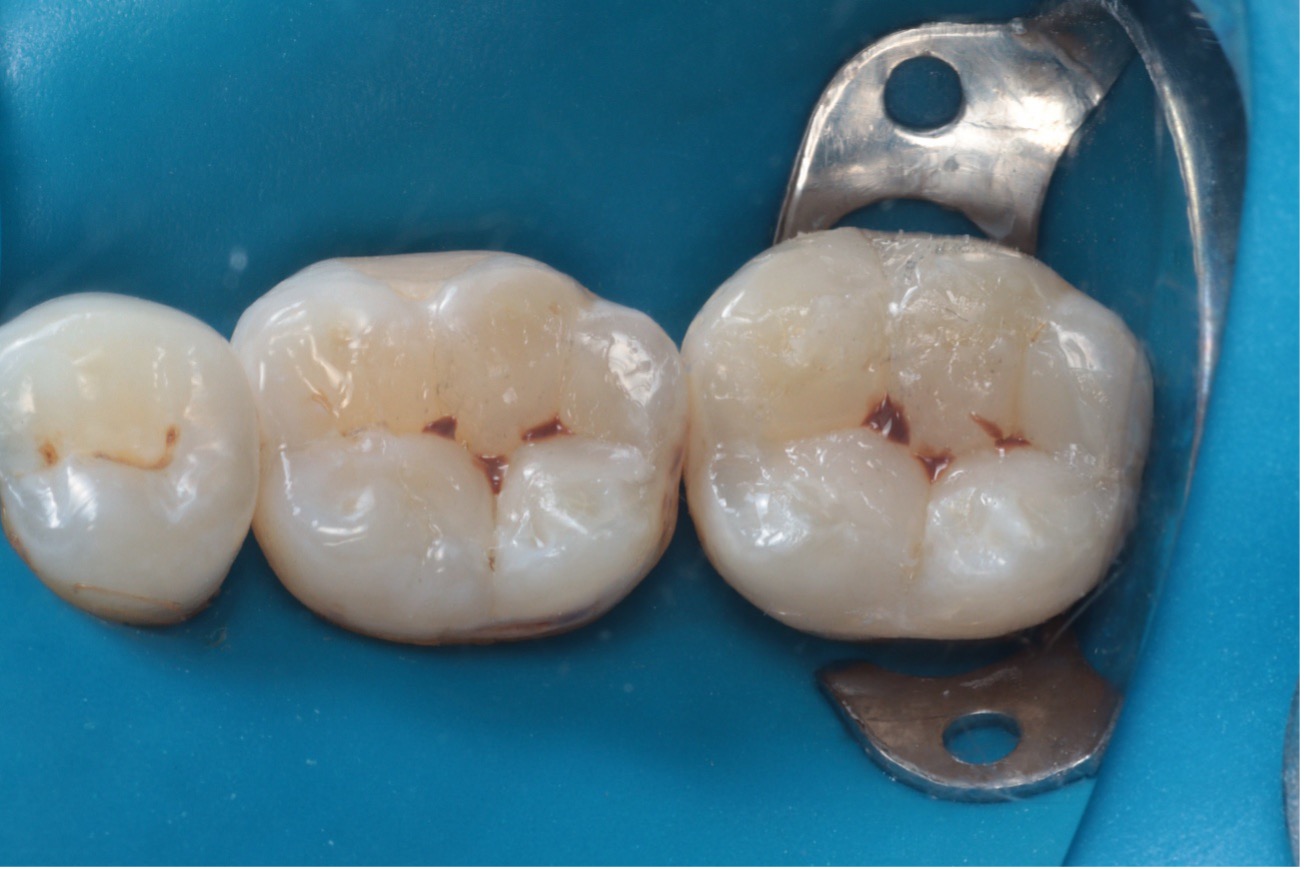

Paciente do sexo feminino, 42 anos, relatou insatisfação com a aparência escurecida de restaurações antigas em amálgama nos dentes 46 e 47. Ao exame clínico, observou-se restaurações metálicas extensas nos dentes posteriores inferiores direitos, sendo classe I no dente 46 e classe V associada à face oclusal no dente 47 (Figura 1).

Figura 1 – Fotografia inicial